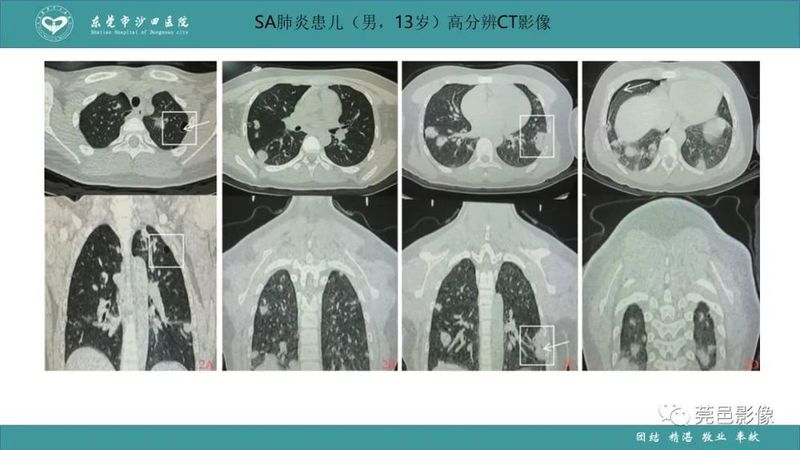

「肺炎克雷伯杆菌肺炎」影像学诊断+鉴别诊断